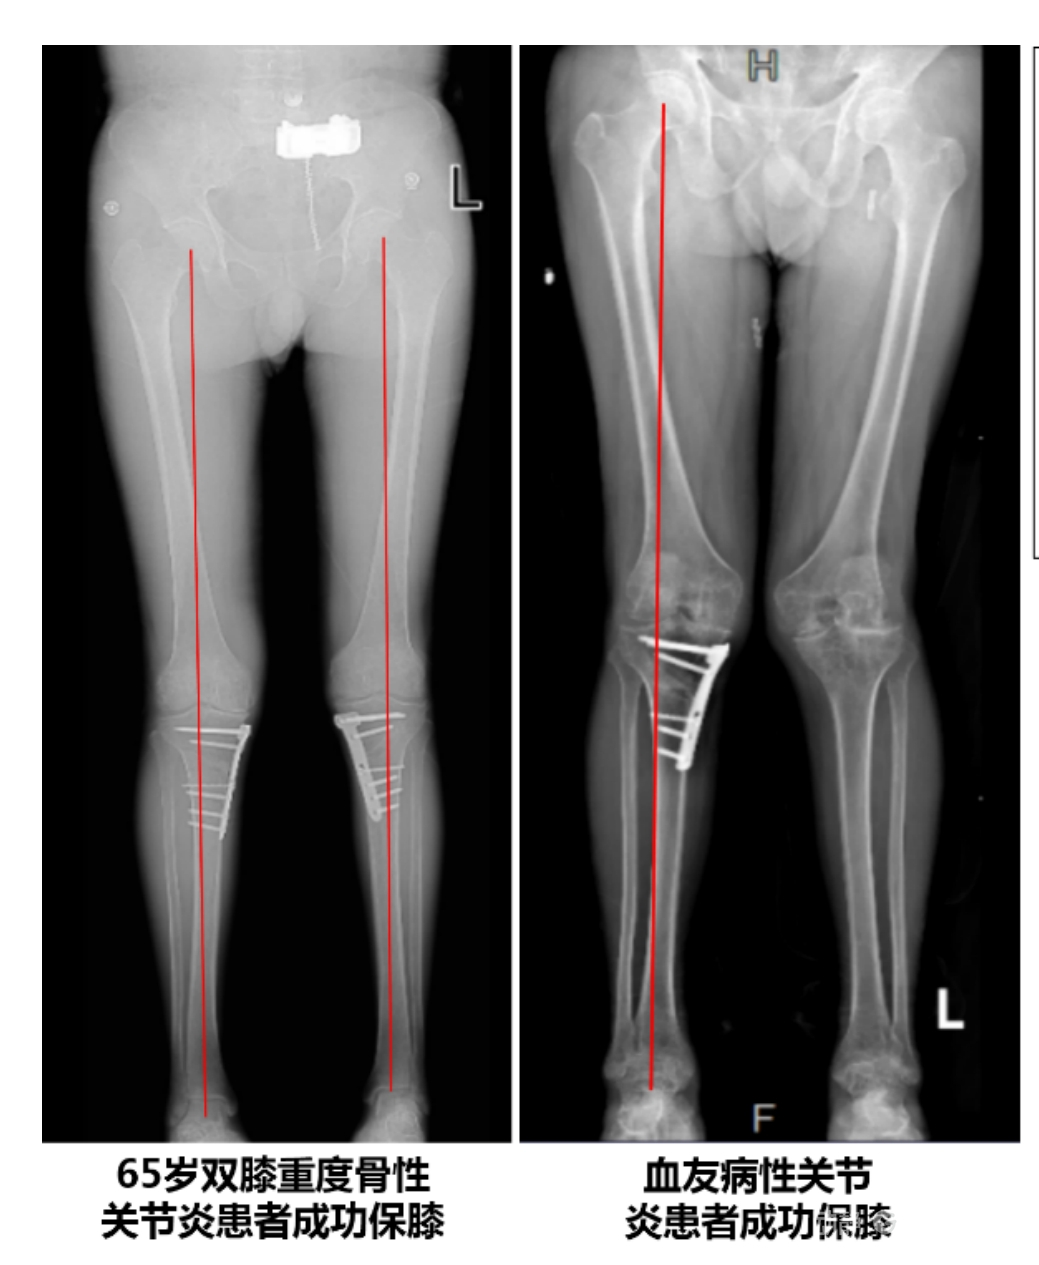

目前,APTT-HTO技術已成功應用于千余名患者,幫助保留自身膝關節。此類保膝手術適用于單間室膝關節炎患者(如 “羅圈腿”),核心是通過調整力線糾正畸形,減輕磨損間室壓力、發揮健康間室作用,延長膝關節壽命。若出現膝關節疼痛、保守治療無效且X線顯示關節間隙部分狹窄,建議及時就醫評估是否適合手術。

APTT-HTO脛骨高位截骨術